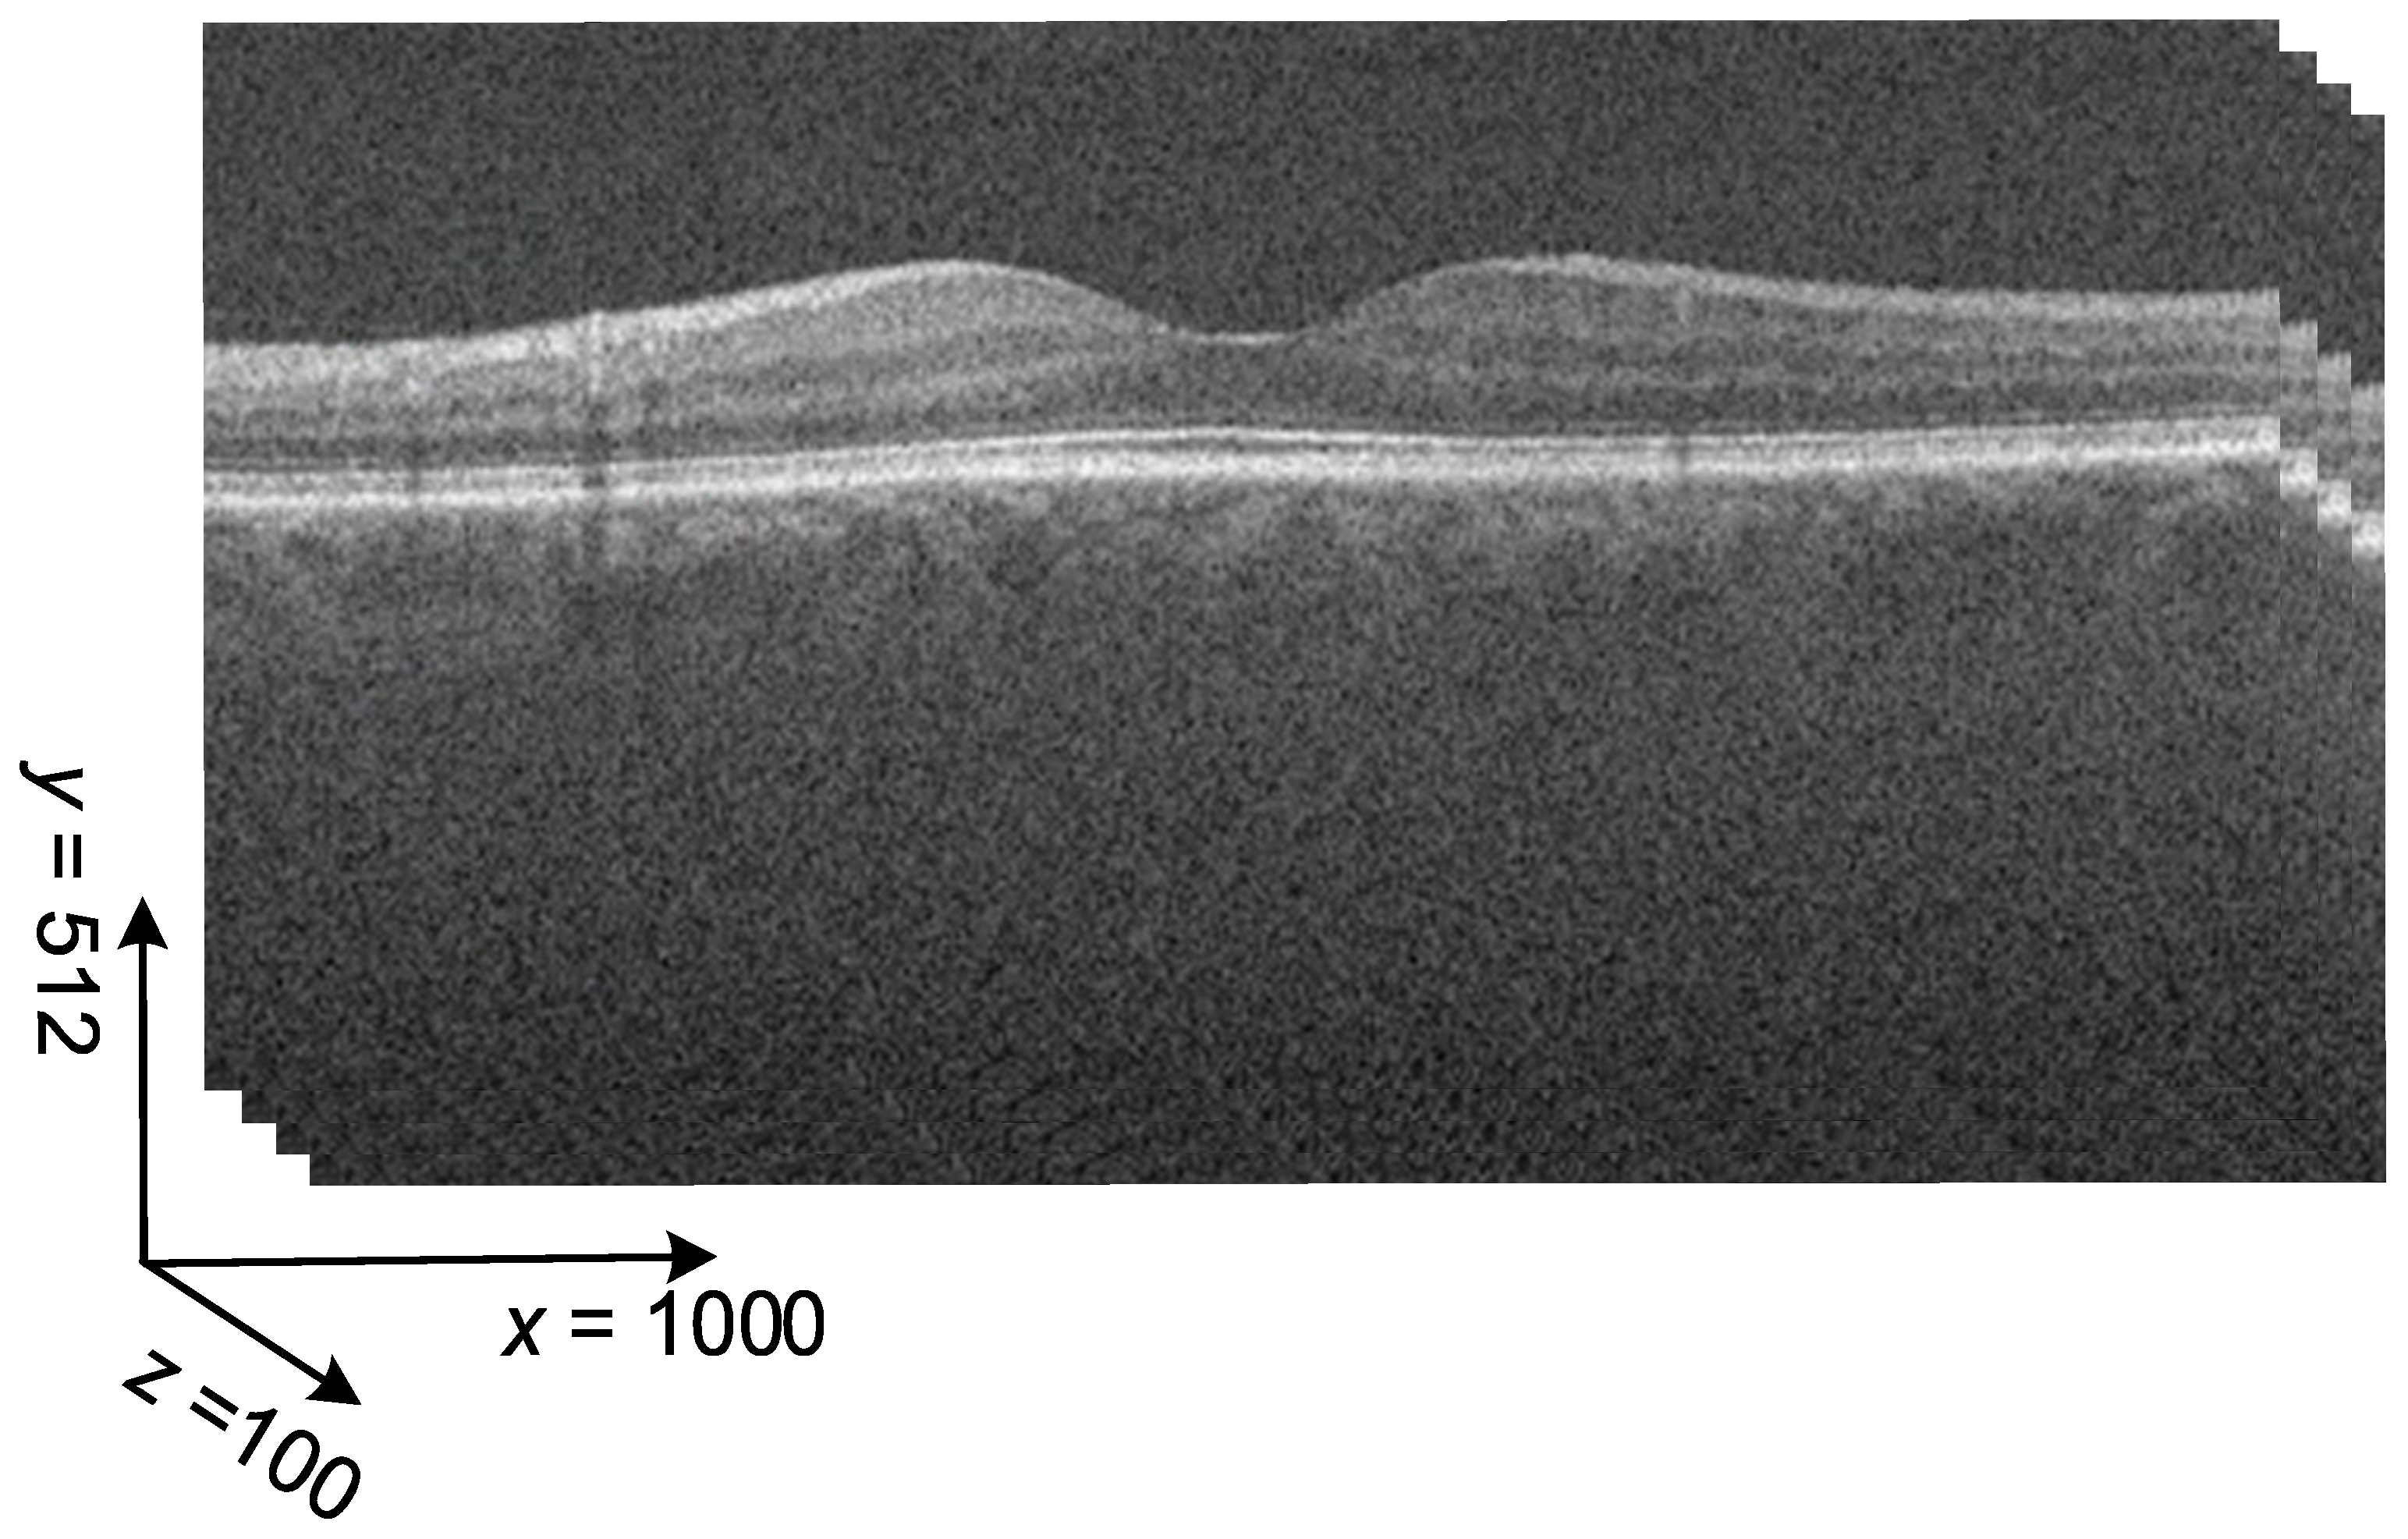

3.1. OCT Dataset